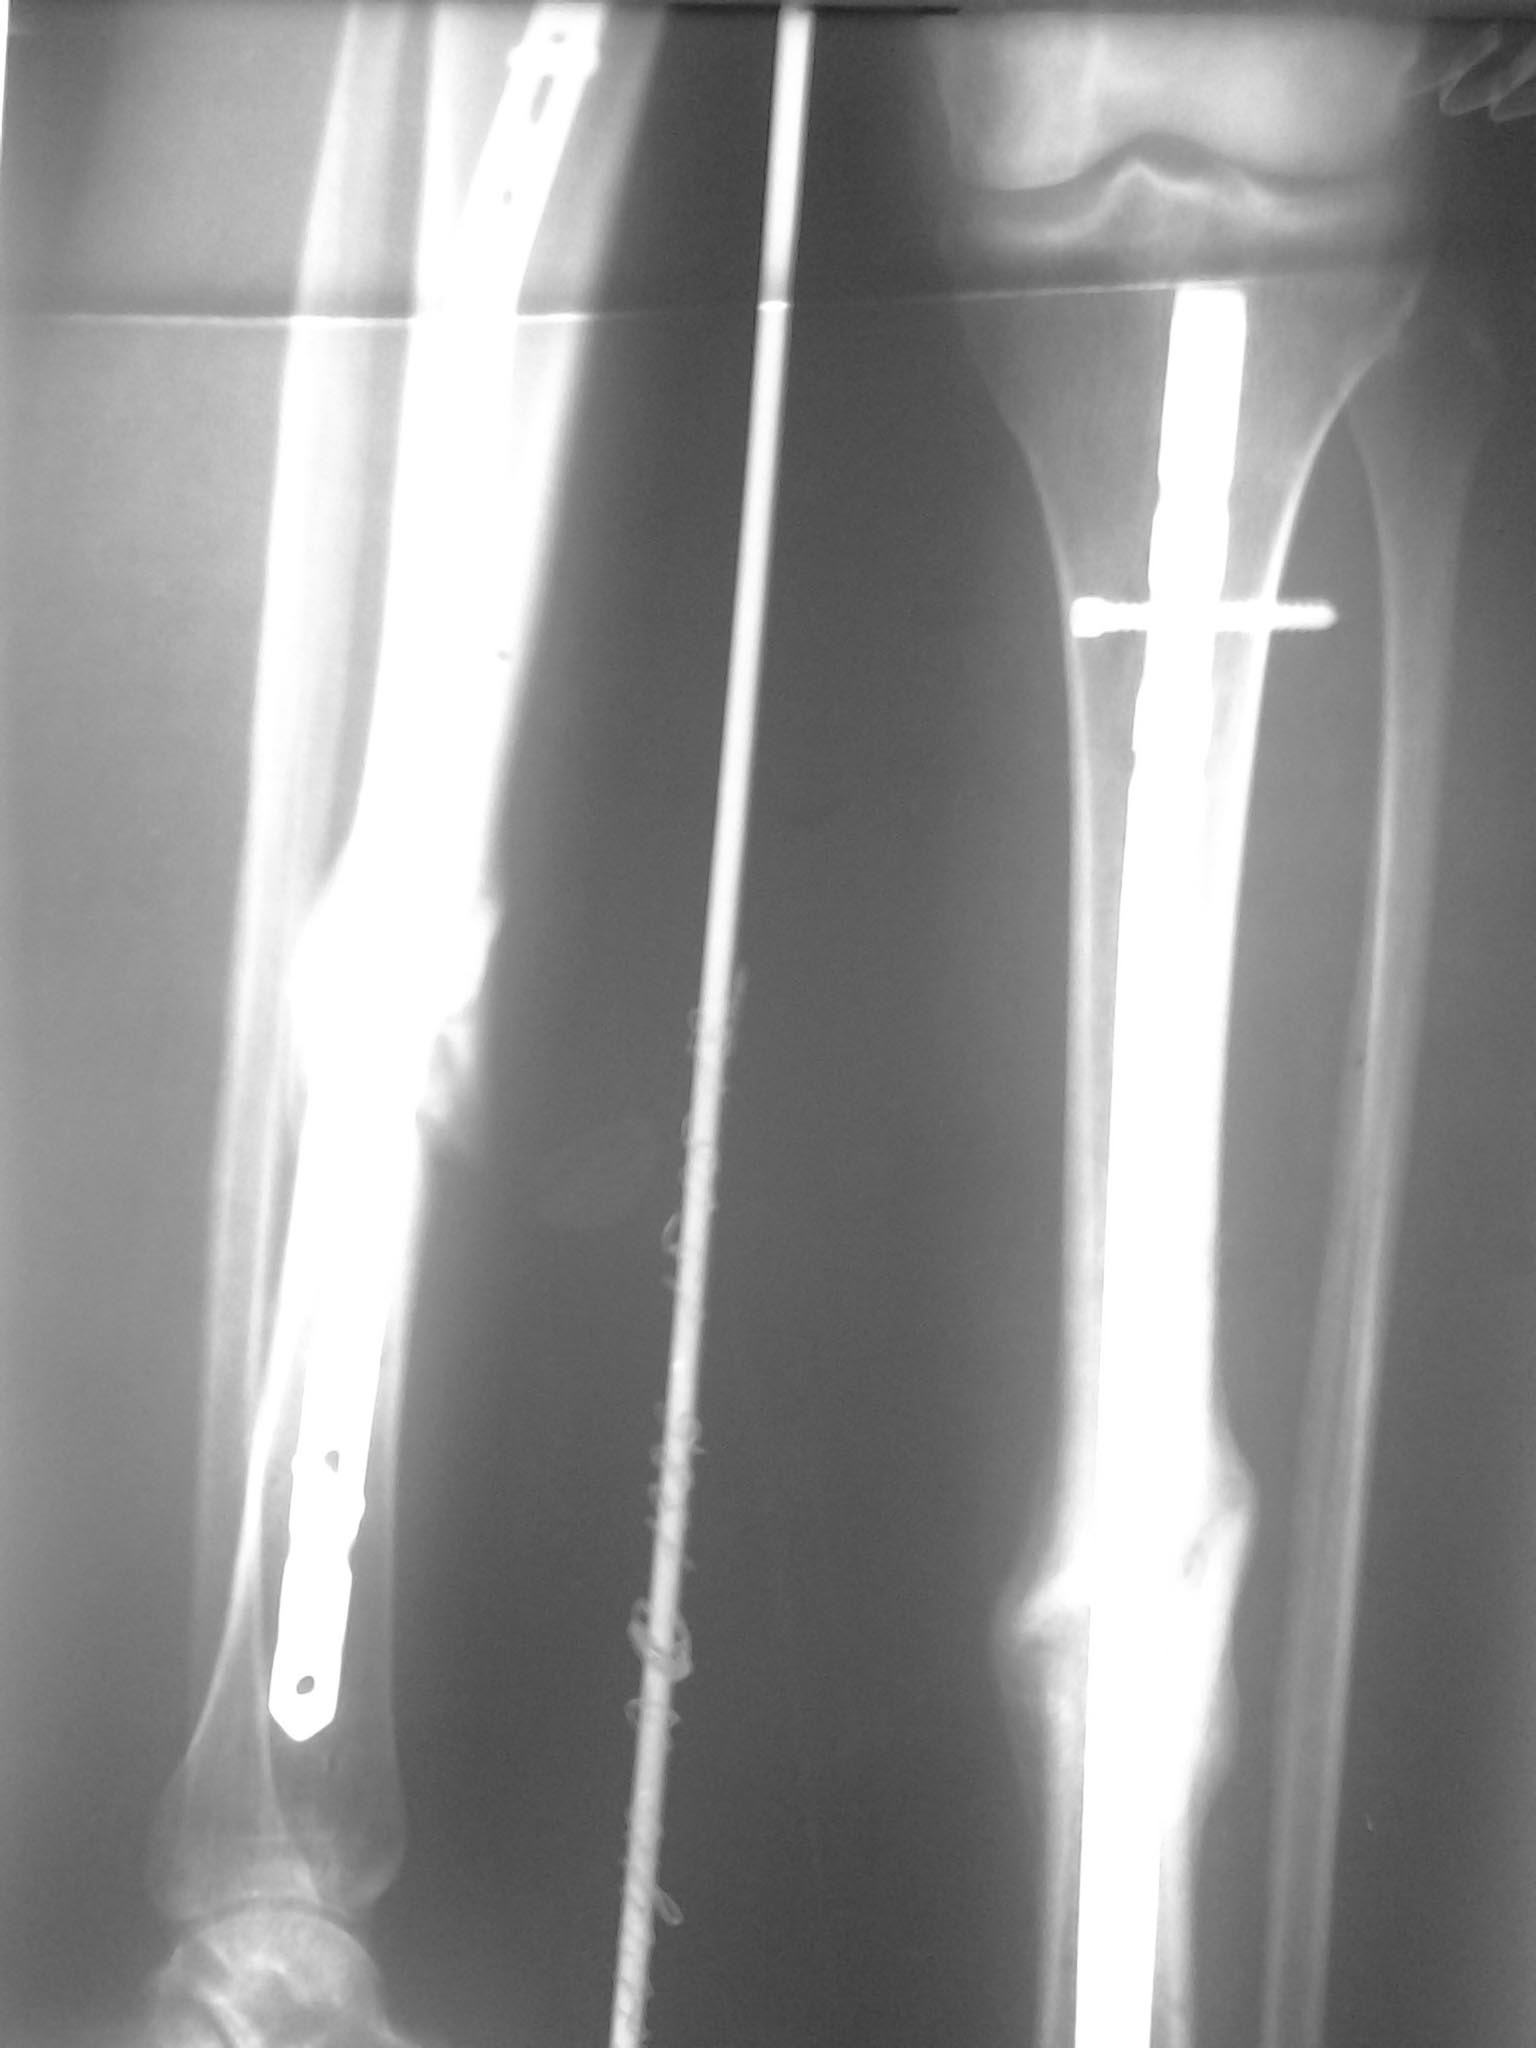

[Ortho] ложный сустав б/берцовой кости на БИОС

общаяя картинка, выложенная щель между отломками прослеживается на

протяжении всего периода сращения.